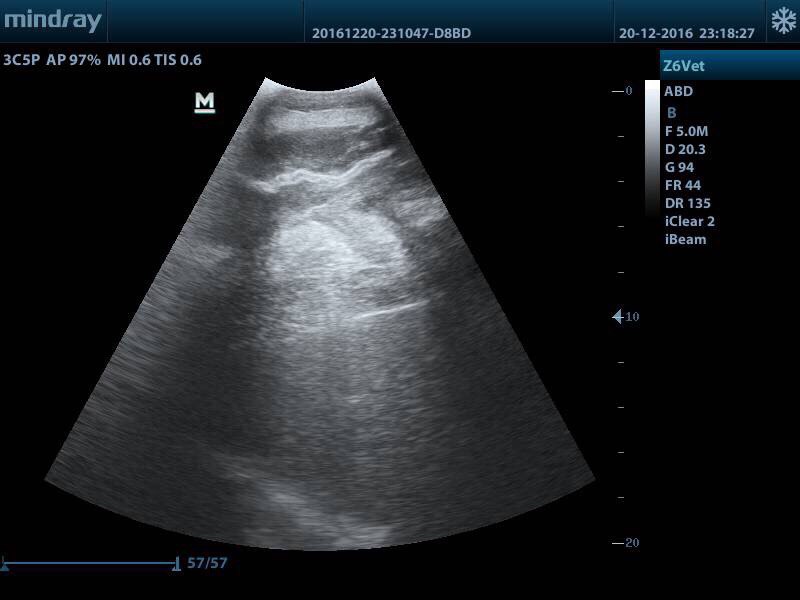

узи.jpg

Вот с такой бедой увезли коня в Максиму

Я же скинула ветеринарное заелючение, у него образовалась серома (полость наполненная жидкостью), затем эта жидкость контаминировала и там образовался абсцесс.